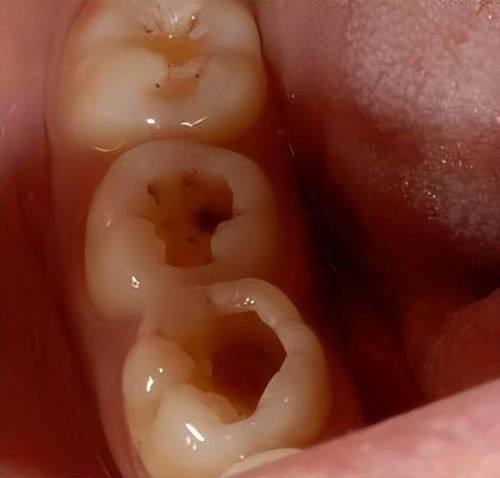

手术治疗之充填法

充填是治疗儿童龋齿的主要手术方法。要是想知道儿童龋齿怎么处理更好,特别多时候充填能起到良好的成效。治疗时,医生会先把龋坏的部分完全去除,接着制备合适的洞型,再对牙齿进行清洗和消毒,末尾用牙科材料把洞填充起来。这样做不仅能修复牙齿的外形,还能防止龋坏继续发展。

不同龋坏程度在充填治疗上也有差异。前龋时进行填充,成效是更好的;中龋进行填充,成效次之;如果是深龋,医生会尽量去除深部的龋坏组织,然后进行护髓、垫底充填。要是在去除龋坏组织的时候已经暴露了牙龈,而且孩子刺激痛症状比较明显,就需要先做牙髓治疗,之后再进行填充;要是去腐露髓孔小,但是刺激痛症状特别剧烈,就可以做直接盖髓后,再进行垫底填充。